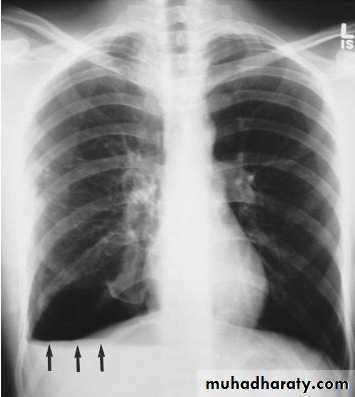

Subpulmonary pleural effusion. On the (A) erect PA and (B) lateral radiograph the effusion simulates a high hemidiaphragm. (C) Ultrasound and (D) CT clearly show that the effusion is located above the diaphragm. Arrows = diaphragmatic area.